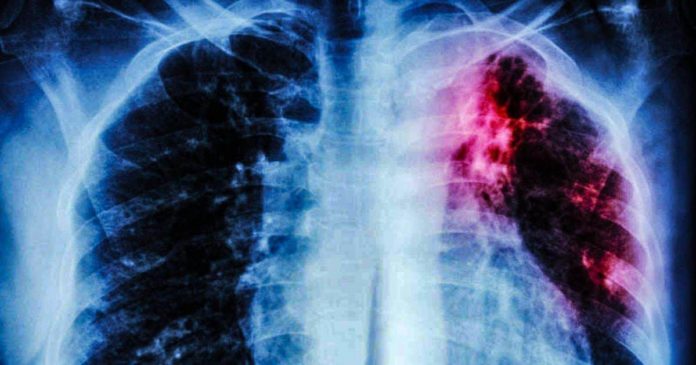

Cabe mencionar que los casos son diagnosticados mediante criterios clínicos, radiológicos o epidemiológicos y son identificados por síntomas, imágenes de rayos X u otros indicadores epidemiológicos.

La tuberculosis es una enfermedad bacteriana infecciosa, que afecta principalmente a los pulmones y es altamente peligrosa. Este padecimiento se propaga cuando una persona infectada tose o estornuda; los síntomas de la enfermedad son tos (algunas veces con sangre), pérdida de peso, sudores nocturnos, fiebre, entre otros y el tratamiento requiere de varios tipos de antibióticos.